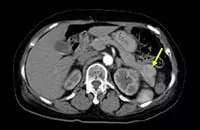

CT画像(インスリノーマ例)**

**:腫瘍を矢印で示す